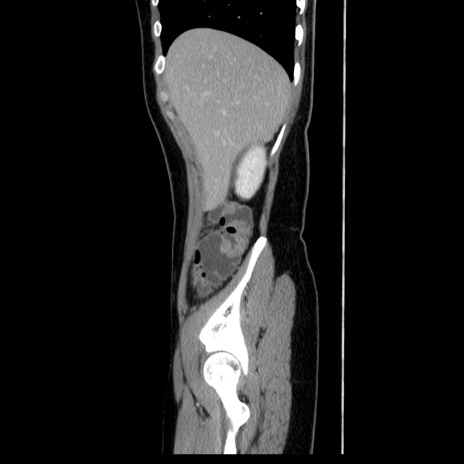

症例39(矢状断像)

【症例】40歳代女性

【主訴】上下腹部痛

【現病歴】2日目から下腹部痛あり。夜間は痛みで眠れなかった。昨日より上腹部痛と下痢が出現。臥位で痛みは軽快したため、休んでいた。本日になって臥位でも立位でも痛みが強くなってきたため救急要請。

【既往歴】子宮内膜症

【身体所見】部:平坦・軟、左上下腹部に圧痛あり、反跳痛あり。

【データ】WBC 21800、CRP 26.78

CT